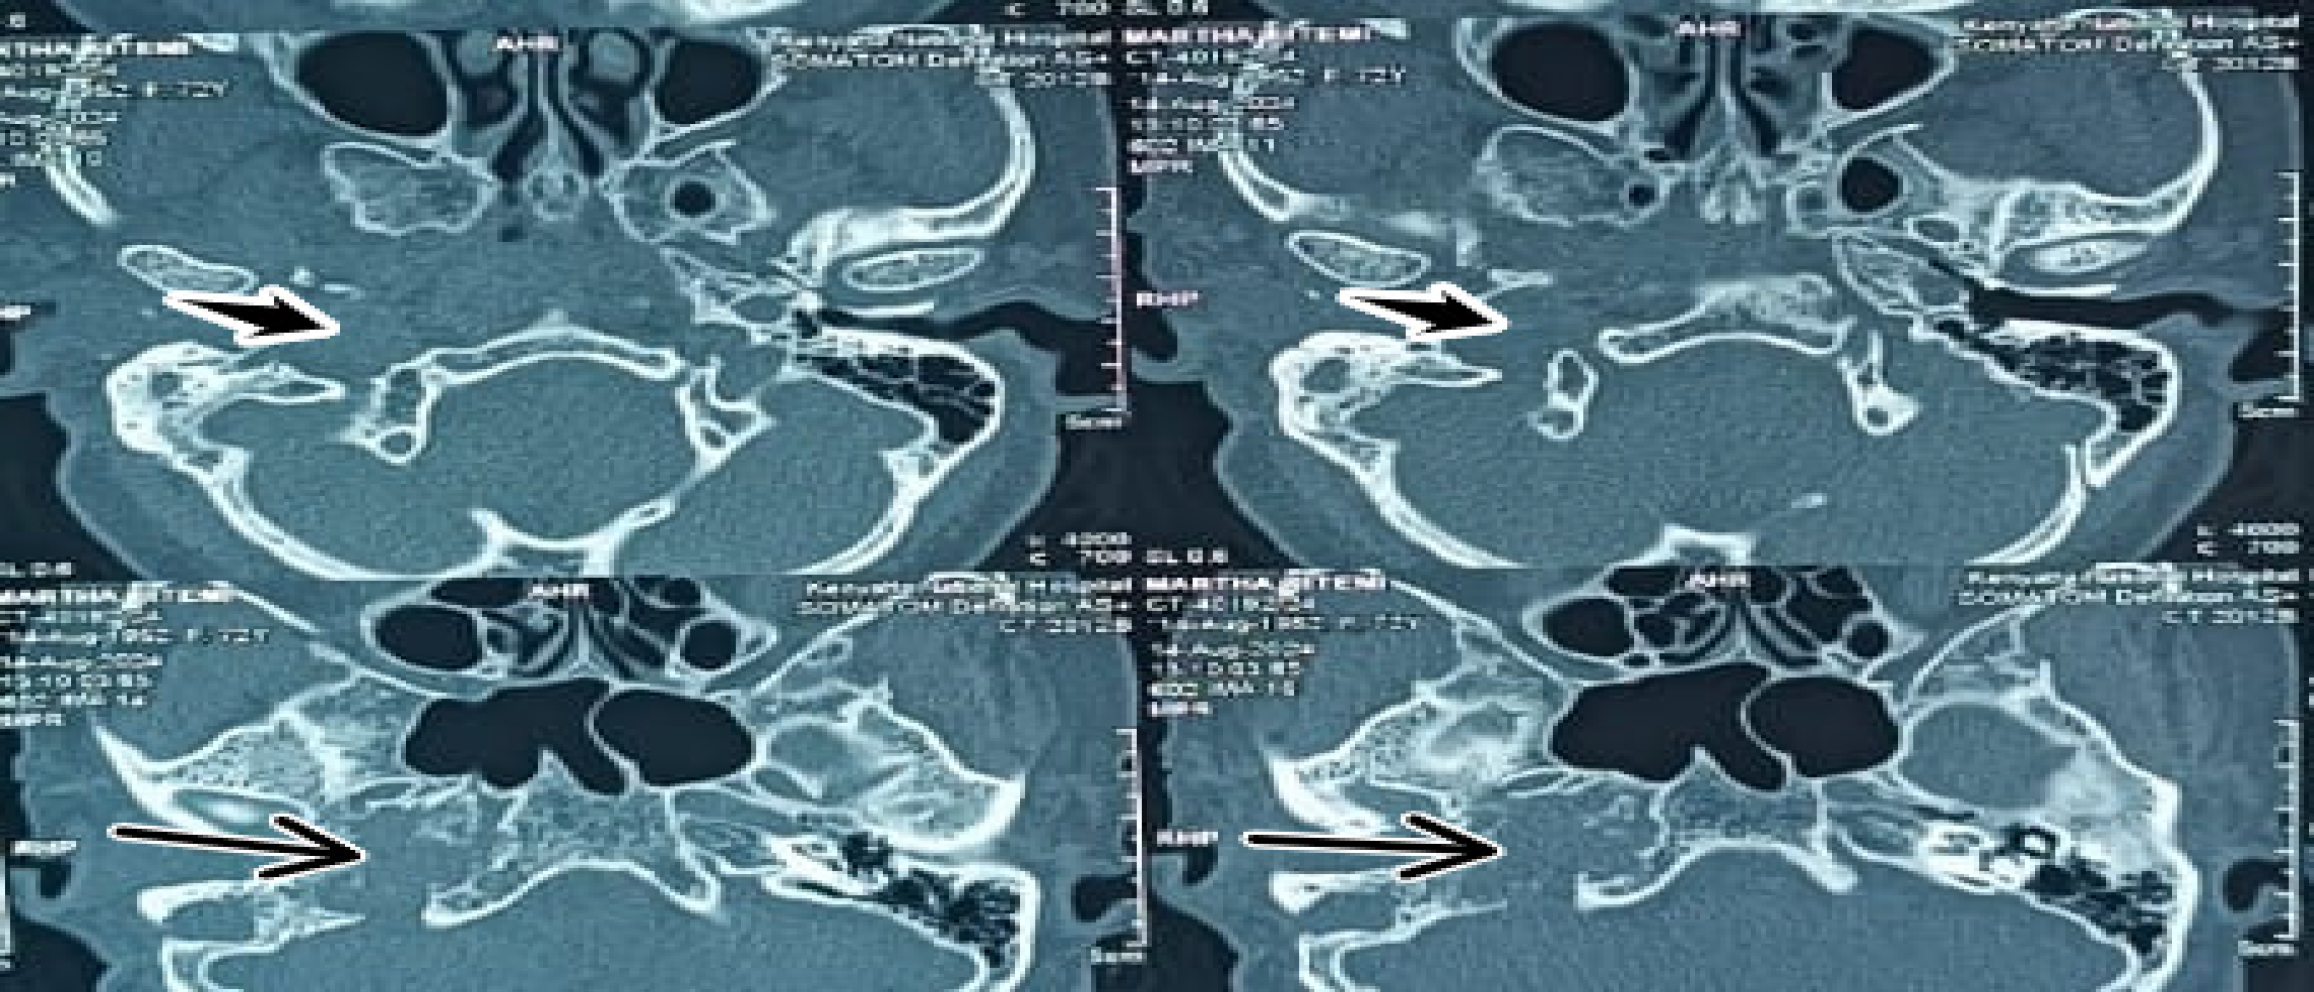

Figure 2 High-resolution non-contrast-enhanced computed tomography of the temporal bone (0.

6-mm slice thickness, bone algorithm reconstruction) showing evidence of prior right mastoidectomy. Permeative bony lesions of the right temporal bone, especially of the temporal apex, right clival region, and right ossicular chain erosion are seen (long thin arrows). The mass is epicentered in the right jugular fossa (short thick arrows).